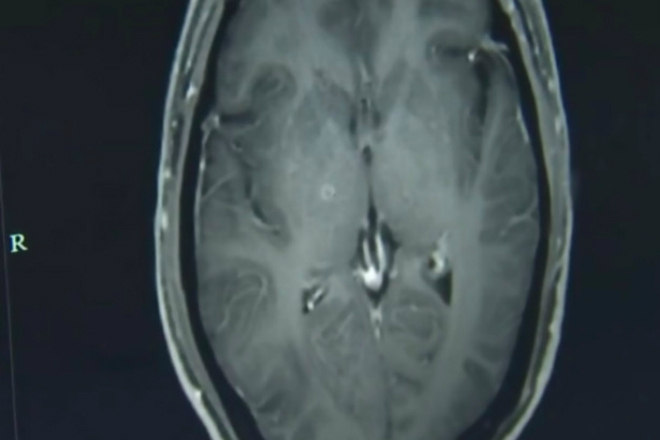

Um homem de 43 anos teve centenas de vermes retirados do cérebro e da região torácica em um hospital da província de Zhejiang, na China

Segundo o jornal New York Post, Zhu Zhongfa chegou ao local alegando sofrer de convulsões e perda repentina de consciência

Exames realizados no paciente mostraram que ele estava contaminado com o verme parasitário Taenia solium

O médico Huang Jianrong explicou que as larvas do verme entraram no corpo de Zhongfa pelo sistema digestório e viajaram por meio da corrente sanguínea até alcançarem o cérebro

Ele foi diagnosticado com cisticercose (corpo) e neurocisticercose (cérebro) e recebeu medicamentos antiparasitário e outros com função de proteger os órgãos de demais danos

Jianrong informou que o paciente tem respondido bem ao tratamento, mas os efeitos da infestação maciça ainda não estão claros